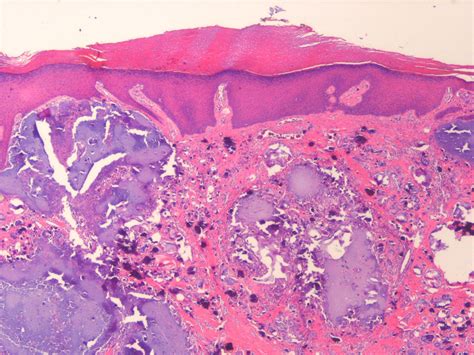

Calcinosis cutis adalah kondisi medis yang ditandai dengan adanya penumpukan kalsium yang berlebihan pada kulit dan jaringan lunak di bawahnya. Kondisi ini dapat terjadi pada siapa saja, baik pria maupun wanita, dan sering kali terjadi pada orang yang menderita penyakit autoimun seperti lupus, skleroderma, atau dermatomiositis.

Untuk mendiagnosis calcinosis cutis, dokter akan melakukan pemeriksaan fisik dan memeriksa riwayat kesehatan pasien. Selain itu, dokter juga dapat melakukan tes darah, tes pencitraan seperti X-ray atau CT scan, dan biopsi jaringan kulit untuk memastikan diagnosis.